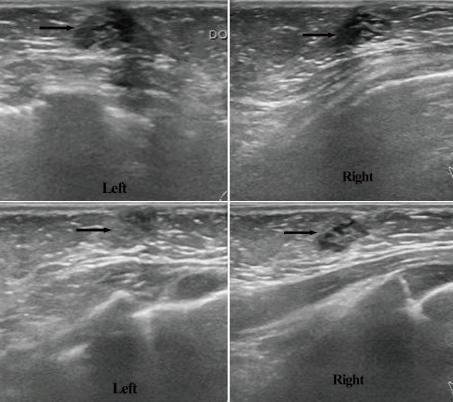

Although milky nipple discharge appears frequently in infants, bloody nipple discharge is a very rare finding. We experienced a 4-month-old, breast-fed infant who showed bilateral bloody nipple discharge with no signs of infection, engorgement, or hypertrophy. The infant's hormonal examination and coagulation tests were normal, and an ultrasound examination revealed mammary duct ectasia. The symptoms resolved spontaneously within 6 weeks without any specific treatment, except that we advised the mother to refrain from taking herbal medicine. Since no such case has been previously reported in Korea, we present this case with a brief review of the literature.

虽然乳头溢乳在婴儿中很常见,但乳头血性溢液却非常罕见。我们遇到一名4个月大的母乳喂养婴儿,出现双侧乳头血性溢液,无感染、乳房胀痛或肥大迹象。婴儿的激素检查和凝血试验均正常,超声检查显示乳腺导管扩张。除了建议母亲停止服用草药外,未进行任何特殊治疗,症状在6周内自行缓解。由于韩国此前未见此类病例报道,我们现报告此病例并简要回顾相关文献。

Mammary duct ectasia in infant breast with bloody nipple discharge: sonographic findings.

J Clin Ultrasound. 2008 May;36(4):229-30. doi: 10.1002/jcu.20407.